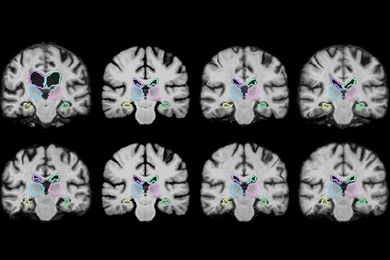

Machine-learning system determines the fewest, smallest doses that could still shrink brain tumors.